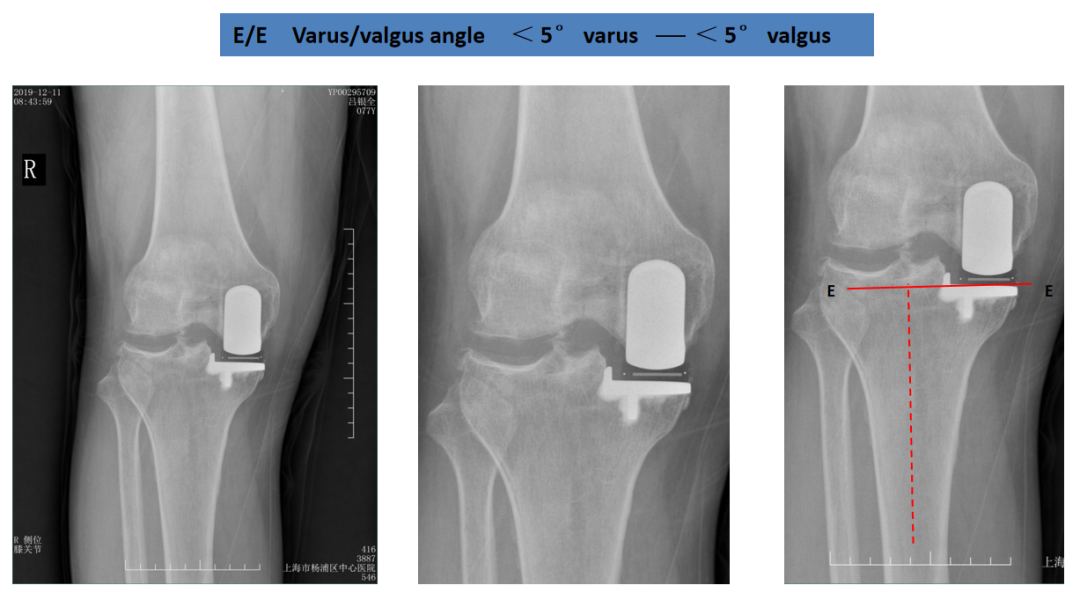

胫骨假体内翻

胫骨假体内翻位:与胫骨AP位中轴线的垂线呈“内翻姿态”。

胫骨假体外翻

胫骨假体外翻位:与胫骨AP位中轴线的垂线呈“外翻姿态”。